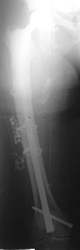

Ein Femurnagel wurde so zugerichtet, dass mit ihm die Prothesenspitze in einer Länge von 8 cm aufgefädelt wurde. Der Nagel wurde durch das Knie hindurch eingebracht. Distal wurde der Nagel verriegelt. Belastungsstabilität lag vor.